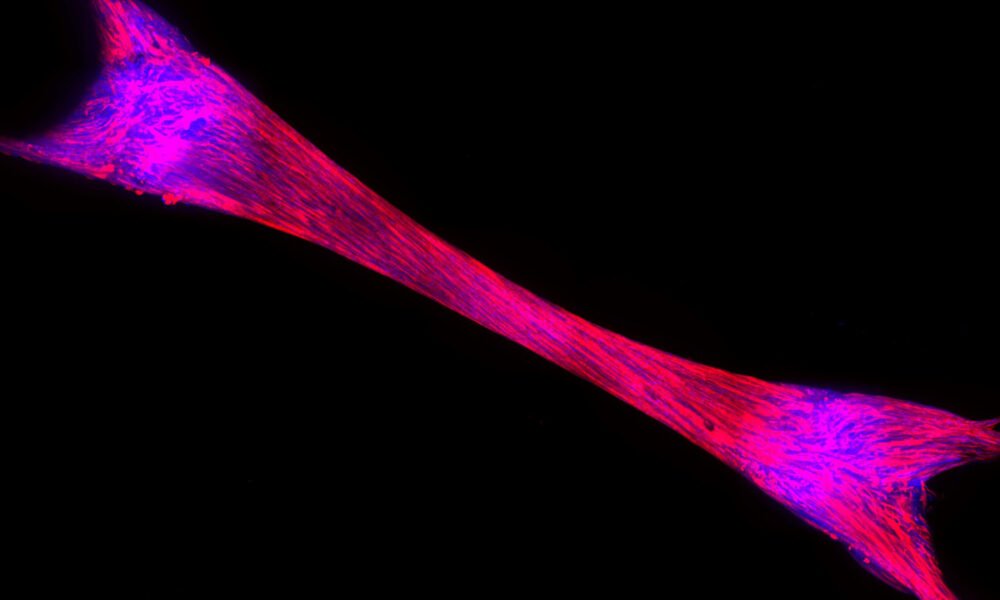

חברת הסטארט אפ ProFuse חושפת טכנולוגיה ראשונה מסוגה בעולם לגילוי תרופות למניעת איבוד מסת שריר במטופלים בתרופות להפחתת משקל. כחלק מהתרחבותה לעולם פיתוח...